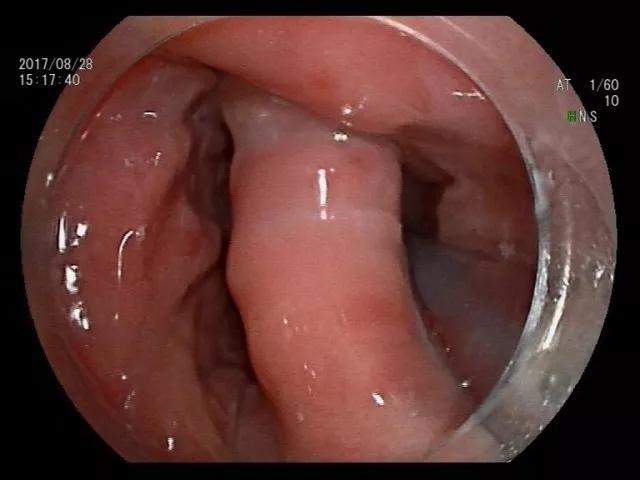

日前他慕名来到南方医科大学深圳医院消化内科就诊,龚伟主任给患者检查胃镜发现食管入口巨大憩室,并可见食物残渣以及液体残留在憩室内,导致出现吞咽困难等症状。

▲术前胃镜可见巨大憩室